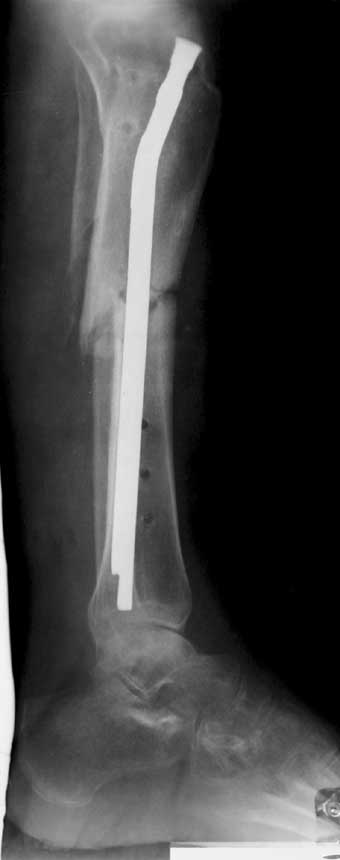

С места аварии в районную больницу, где произвели ампутацию правой голени. Дальше в клинику спец. помощи, где на левой голени были удалены нежизнеспосбные инфицированные отломки, (дефект 13 см) и наложен аппарат Гофмана. Детали неизвестны. Со слов больного, инфекционный процесс левой голени купирован не был. В феврале аппарат был снят и произведен остеосинтез гвоздем (before1;2). В мае, объективно: В нижней трети голени функционирует свищ, отделяемое гнойное: золотистый стафилокок, чувствительный к большинству антибиотиков.

1 июня произведено удаление гвоздя, дренаж костномозгового канала, остеосинтез аппаратом Илизарова ( after 1; 2).

Рентгенологически определяется дистракционный регенерат удовлетворительной плотности и наличие в нем полости (now 1;2;3).